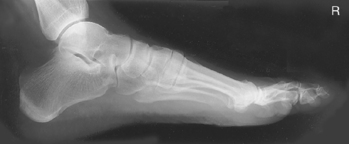

• Recumbent, turned on affected side, knee flexed with unaffected leg behind to prevent overrotation

• Place support under affected knee and leg as needed to place plantar surface of foot perpendicular to IR for a true lateral.

Lateral projection is most common for longitudinal arch (flat feet), AP demonstrates alignment of metatarsals and phalanges.